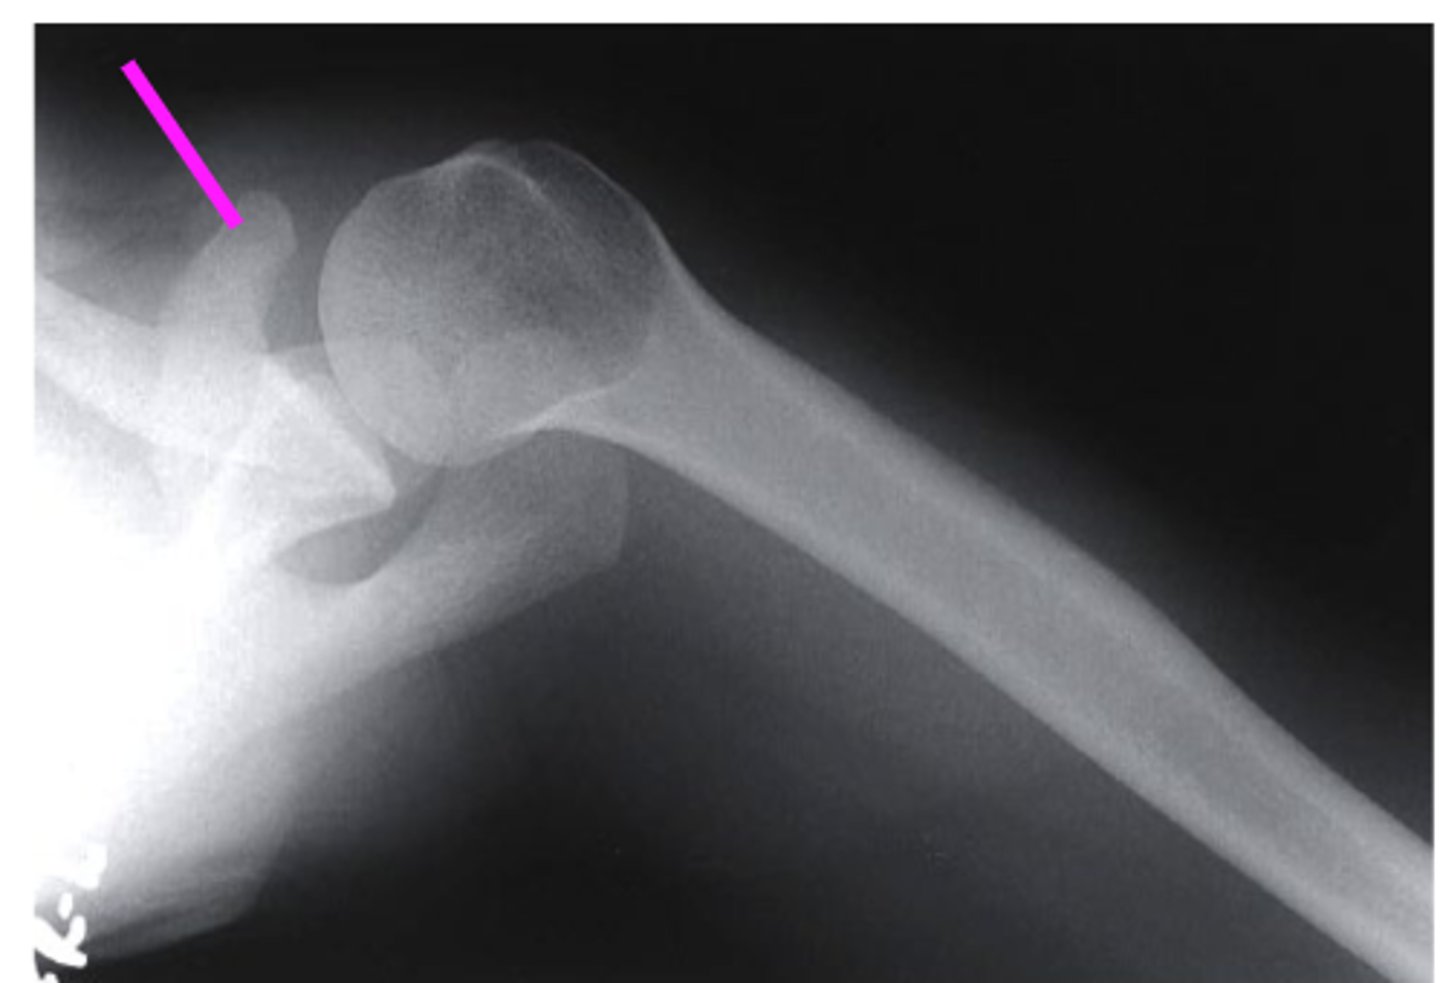

AP + ER

What view is this?

clavicle

what does the pink line point to?

spine of scapula

coracoid process

AC joint

acromion

Humeral Head

Greater Tuberosity

lesser tuberosity

Anatomic Neck of Humerus

Surgical Neck of Humerus

Shaft of Humerus

glenoid fossa

body of scapula

axillary border of scapula

vertebral border of the scapula